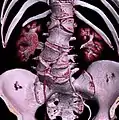

Several congenital block vertebrae in the transition from the thoracic to the lumbar spine and hemivertebrae.

Congenital block vertebra in the lumbar spine (partial vertebrae 3 and 4). The rear portion of the disc still exists.